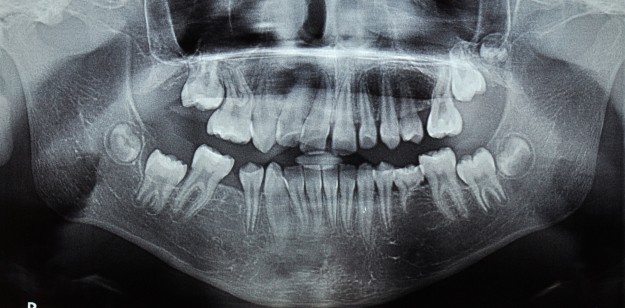

За да се достигне до решение за избор на екстракционно или безекстракционно оротодонтско лечение е необходимо да се съобразим с недостига на място в зъбната дъга и продължителността на лечението. За това си поставихме за цел да съпоставим тези параметри.